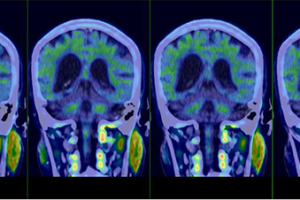

臨床基礎齊發力 阿爾茨海默病雙突破